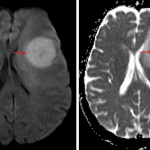

MRI

- T1 hypointense, T2 isointense mass with a rim of relative T1 signal hyperintensity and T2 signal hypointensity in the left frontal lobe measuring 3.4 x 3.3 x 3.2 cm with finger-like enhancing projections and a satellite enhancing lesion more superiorly in the left frontal lobe

- Homogeneous, diffuse corresponding enhancement and restricted diffusion

- No associated susceptibility artifact

- Surrounding vasogenic edema and corresponding mass effect resulting in local sulcal effacement, crowding of the left lateral ventricle, and left-to-right midline shift measuring 4 mm

- No downward herniation or hydrocephalus